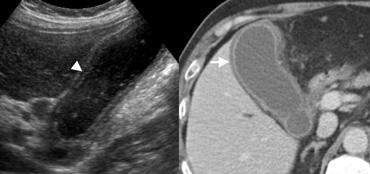

Phụ nữ 43 tuổi với viêm túi mật cấp có sỏi. CT có thuốc cản quang cho thấy túi mật căng giãn (đầu mũi tên) với thành hơi dày và thâm nhiễm mỡ quanh túi mật mờ nhạt (dấu hoa thị). Có một viên sỏi gây tắc nghẽn kẹt tại cổ túi mật (mũi tên).

Viêm túi mật cấp

Viêm túi mật cấp là nguyên nhân phổ biến thứ tư khiến bệnh nhân nhập viện vì đau bụng cấp [4], và đây là chẩn đoán hàng đầu cần nghĩ đến khi phát hiện thành túi mật dày trên hình ảnh học.

Các dấu hiệu hình ảnh bổ sung hỗ trợ chẩn đoán viêm túi mật cấp có sỏi bao gồm:

- Sỏi túi mật gây tắc nghẽn

- Túi mật giãn căng do ứ dịch

- Dấu hiệu Murphy dương tính trên siêu âm (tức là đau khi ấn đầu dò siêu âm trực tiếp lên vị trí túi mật)

- Viêm mỡ quanh túi mật hoặc tràn dịch quanh túi mật

- Tăng sinh mạch thành túi mật trên Doppler năng lượng.

Bên trái là hình ảnh của bệnh nhân nam 62 tuổi với viêm túi mật cấp có sỏi.

Siêu âm cắt ngang tại vị trí đau tối đa cho thấy túi mật căng giãn do ứ dịch, thành dày, không thể ép xẹp (đầu mũi tên), với sỏi trong lòng túi mật và cặn lắng hoặc mảnh vụn.

CT có thuốc cản quang cho thấy viêm mỡ lan rộng (đầu mũi tên) bao quanh túi mật (mũi tên).

Bệnh nhân nam 74 tuổi với viêm túi mật cấp không có sỏi. TRÁI: Siêu âm tại vị trí đau tối đa cho thấy thành túi mật dày (mũi tên), lòng túi mật chứa đầy cặn lắng (dấu hoa thị) mà không có sỏi. PHẢI: Siêu âm Doppler năng lượng cho thấy tăng sinh mạch thành túi mật (đầu mũi tên), là dấu hiệu hỗ trợ chẩn đoán viêm.

Viêm túi mật không có sỏi

Viêm túi mật cấp không có sỏi chủ yếu xảy ra ở bệnh nhân nặng, được cho là do độ nhớt mật tăng cao từ việc nhịn ăn và các thuốc gây ứ mật.

Các đặc điểm hình ảnh tương tự như viêm túi mật cấp, ngoại trừ việc không có sỏi trong khi cặn lắng túi mật thường hiện diện (Hình).

Do ở bệnh nhân nặng, các bất thường túi mật thường gặp thứ phát do bệnh lý toàn thân (xem bên dưới), viêm túi mật không có sỏi có thể khó chẩn đoán [5].

Ở những bệnh nhân này, dẫn lưu túi mật qua da vừa có giá trị chẩn đoán vừa có tác dụng điều trị.